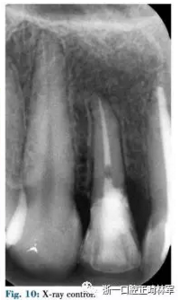

正畸牽引結束(圖7)時,皮瓣抬高后使用橡皮障暴露邊緣(圖8),進行纖維樁修復,堆好核后使用層壓瓷貼面修復(圖9-11)。